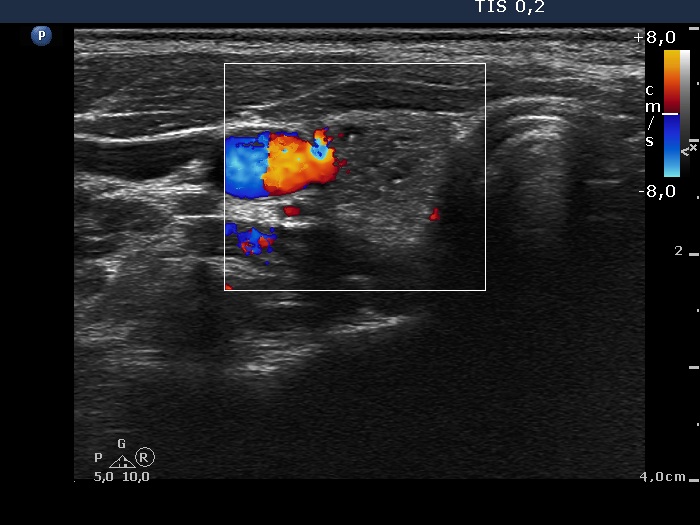

Ultrasonography: The thyroid was echonormal. There was a moderately hypoechogenic inhomogeneous nodule in the lower pole of the right lobe. There were two lymph nodes next to each other above the right thyroid in the submandibular area. The lymph nodes presented a regular hilum.

1. This is the typical presentation of a bacterially infected lymph node. In most of these cases we find multiple lymph nodes next or very close to each other. The presence of ill-defined hypoechogenic areas within the lymph nodes is an even more important sign of a bacterial lymphadenitis.